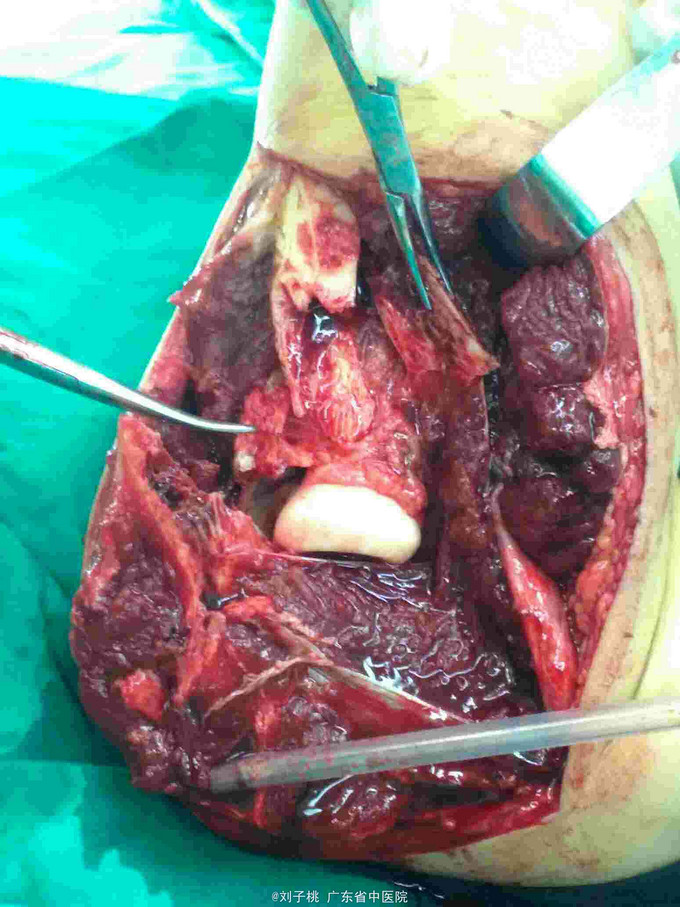

#骨科科室play#右肘开放性孟氏骨折

骨折 尺神经断裂 孟氏骨折

25岁男性,刀砍伤右肘致疼痛畸形入院。既往体健,无过敏史。

右肘开放性孟氏骨折,尺神经断裂,急诊行清创内固定加神经修复。